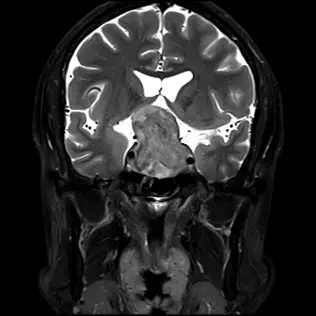

56歲男性,主訴近 2年來雙側視力模糊,頭部磁振造影檢查結果如附圖,下列何者為最可能之診斷?

本題考查鞍部腫瘤(Sellar tumors)的鑑別診斷,重點在於影像學特徵與臨床症狀的對應。核心概念是辨識腦下垂體巨腺瘤(Pituitary macroadenoma)在 MRI 上的典型「雪人徵」(Snowman sign)或「8字形徵」(Figure-of-8 sign),以及其向上壓迫視交叉導致的視力障礙。

- 檢查方式:腦部 MRI 冠狀切面(Coronal view),從腦室與腦溝內的腦脊髓液(CSF)呈現高訊號(亮白色)判斷,此為 T2 加權影像(T2-weighted image)。

- 病灶位置:影像中央可見一個巨大的腫塊(Mass),佔據了蝶鞍(Sella turcica)並向鞍上池(Suprasellar cistern)延伸。

- 形態特徵:腫塊呈現典型的**「雪人狀」(Snowman appearance)**或「8字形」。

- 下半部:位於蝶鞍內,體積較大,將蝶鞍骨質擴大。

- 中間束腰:腫瘤向上生長穿過**鞍膈(Diaphragma sellae)**開口時受到限制與束縛,形成狹窄的「腰部」。

- 上半部:穿過鞍膈後在鞍上池空間再次膨大。

- 質量效應(Mass Effect):

- 上方:腫瘤上半部明顯向上頂撞並壓迫視交叉(Optic chiasm)。視交叉受壓是導致患者「雙側視力模糊」(臨床上典型為雙顳側偏盲,Bitemporal hemianopsia)的主因。

- 兩側:腫瘤緊鄰兩側的海綿竇(Cavernous sinus),兩側海綿竇內的黑色圓形空洞為頸內動脈(Internal Carotid Artery)的流空效應(Flow void),顯示動脈位置被推擠但未見明顯包覆或阻塞。

- 訊號強度:腫塊訊號與大腦灰質相似(Isointense),質地相對均勻。

患者為中年男性,出現漸進式雙側視力模糊,MRI 顯示一源自蝶鞍並向鞍上延伸的實質性腫塊。腫塊因鞍膈束縛呈現經典的**「雪人徵」(Snowman sign),並向上壓迫視交叉。這些特徵是腦下垂體巨腺瘤(Pituitary Macroadenoma)**的教科書級表現。腫瘤壓迫視交叉導致的視力損害(通常是雙顳側視野缺損)解釋了患者的主訴。

- 雪人徵(Snowman Sign):腦下垂體巨腺瘤的特徵性影像,描述腫瘤在通過鞍膈(Diaphragma sellae)時被束縮,形成像雪人或數字 "8" 的形狀。